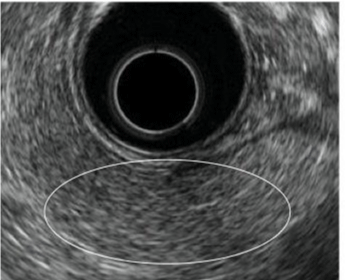

Normal Pancreas on EUS

An understanding of normal pancreas on EUS is extremely important for making EUS diagnosis of CP. The normal pancreatic parenchyma is uniformly depicted in equal or a slightly less hyperecho to the liver; it presents a so-called fine reticular pattern. The main duct dilation, duct irregularity and side branch ectasia are not visualized within the parenchyma [8]. Furthermore, the main ductal wall is observed as a uniform and slightly hyperlinear echo: 2.4 mm diameter in the head, 1.8 mm in the body, and 1.2 in the tail [6]. The EUS image of CP is defined based on these views. The EUS image of a normal pancreas is presented in figure 1.